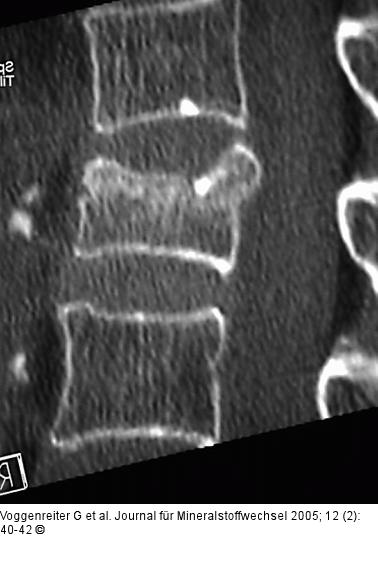

Abbildung 4a-d: Wirbelkörperaufrichtung - postoperative Darstellung Postoperative Darstellung der Zementverteilung und der Wirbelkörperaufrichtung im CT. Trotz Beteiligung der Wirbelkörperhinterkante kam es zu keiner weiteren Einengung des Spinalkanals, sondern durch Ligamentotaxis eher zu einer Erweiterung. Das postoperative Kontroll-CT zeigt eine Reduktion der Kyphose bei klinischer Beschwerdefreiheit der Patientin. |

Postoperative Darstellung der Zementverteilung und der Wirbelkörperaufrichtung im CT. Trotz Beteiligung der Wirbelkörperhinterkante kam es zu keiner weiteren Einengung des Spinalkanals, sondern durch Ligamentotaxis eher zu einer Erweiterung. Das postoperative Kontroll-CT zeigt eine Reduktion der Kyphose bei klinischer Beschwerdefreiheit der Patientin. |